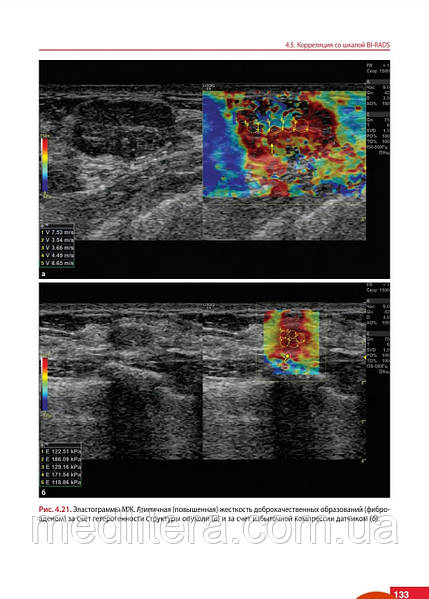

У монографії розглянуті питання застосування ультразвукової еластографії в клінічній практиці з урахуванням актуальних практичних і клінічних рекомендацій. Детально описана методика проведення еластографії різних внутрішніх і поверхнево розташованих органів, принципи інтерпретації результатів, чинники, що впливають на конкретний результат і ефективність, коректність і відтворюваність кількісних і якісних показників еластоографії.